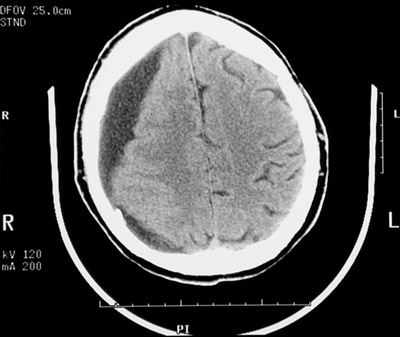

| There is a chronic subdural hematoma beneath the dura with a serrated edge interfacing with the underlying cortex. Note the effacement of the right lateral ventricular system. The view below is at a higher level near vertex. This older patient has some cerebral atrophy. |